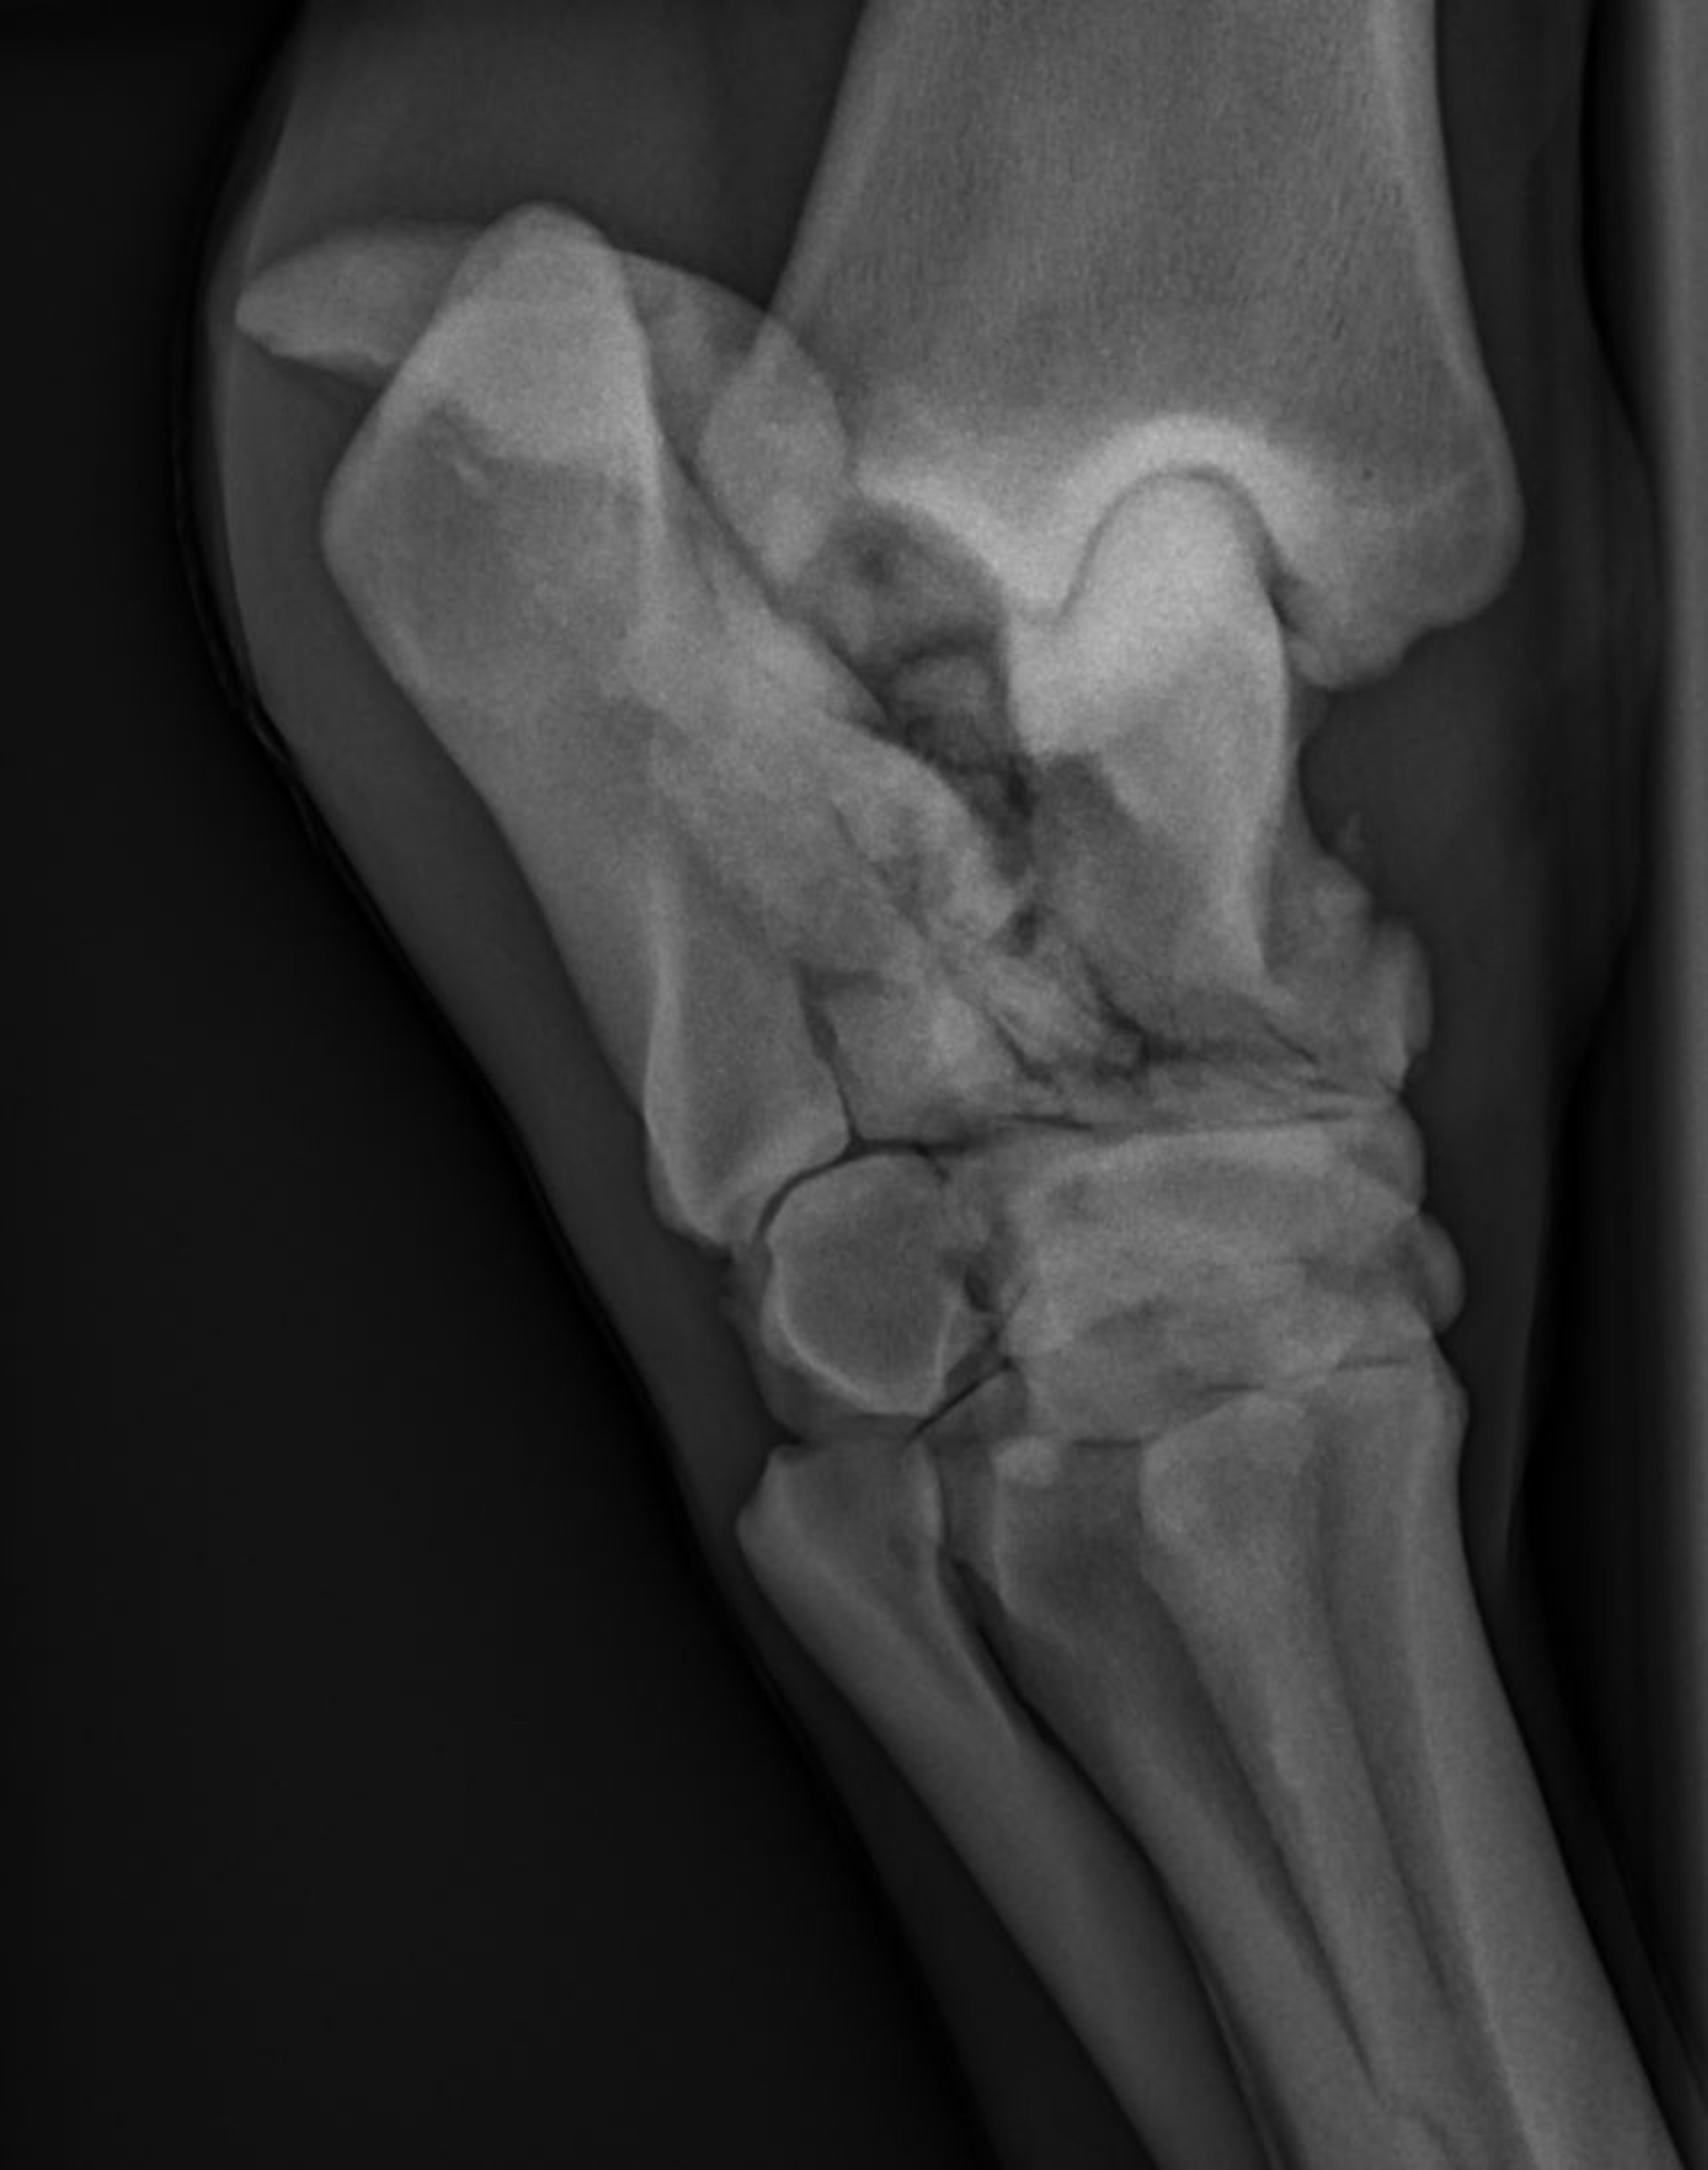

Dorsolateral-plantaromedial radiograph of a horse, showing a severely comminuted fracture of the talus and calcaneus.